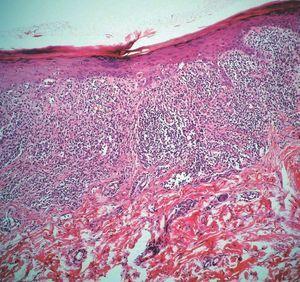

Con la sospecha de liquen plano (LP) con afectación esofágica se realizó una biopsia cutánea de las lesiones orales y lumbares que demostró la presencia de un denso infiltrado linfocitario en la dermis alta y degeneración vacuolar y hendiduras dermoepidérmicas como hechos comunes en ambas biopsias e hiperqueratosis ortoqueratósica, hipergranulosis, acantosis en dientes de sierra y cuerpos de Civatte en las lesiones cutáneas (figs. 4 y 5). Los estudios de inmunofluorescencia directa (IFD) e inmunofluorescencia indirecta (IFI) fueron negativos. Otras pruebas complementarias solicitadas, entre las que se incluyeron hemograma y bioquímica completos, proteinograma, radiografía de tórax, anticuerpos antinucleares (ANA), serología del virus de la hepatitis B (VHB) y de la hepatitis C (VHC), se encontraban dentro de la normalidad. Se instauró tratamiento con corticoides orales en dosis de 30 mg de prednisona oral al día con buena evolución de las lesiones y mejoría de los síntomas orales y esofágicos al mes de evolución, momento en el cual la paciente regresó a su lugar de residencia habitual.

Figura 4. Mucosa oral. Infiltrado linfocitario en dermis alta y degeneración vacuolar (hematoxilina-eosina, x200).

Figura 5. Lesión de la piel. Hipergranulosis con acantosis en dientes de sierra, disqueratosis e infiltrado linfocitario en banda (hematoxilina-eosina, x100).